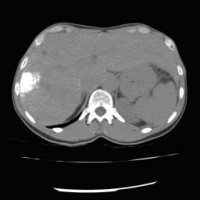

« Zurück Computertomographische Dokumentation der Embolisateinlagerung innerhalb des Tumors nach transarterieller Chemoembolisation (TACE) (Bild 2 von 5) Vorwärts »